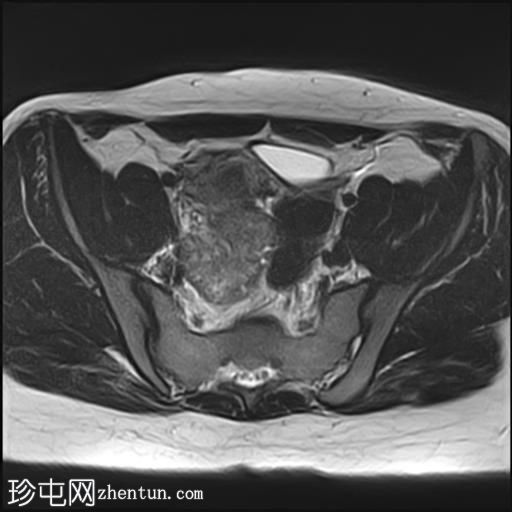

轴位T1加权像

增强脂肪抑制像

其中一个位于子宫上方,T2加权像呈中等信号,中心区域呈高信号,增强T1脂肪抑制像未见强化。右侧卵巢增大,增厚的血管蒂扭曲,未见强化,轴位和矢状位T2加权像均显示清晰。

另一个位于子宫后窝,T2加权像呈中等信号,增强扫描显示明显强化。

2个月前进行的MRI检查显示双侧卵巢肿块均有强化,右侧卵巢肿块未见扭转。